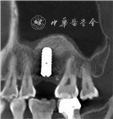

(5)治疗过程:①一期手术,见图2。术前设计腭侧旋转瓣(图2A)。抽取患者静脉血20 ml,离心(Medifuge MF200离心机,Silfradent,意大利)制备浓缩生长因子(concentrated growth factors,CGF)。患者取仰卧位,口内外消毒,铺巾。局部浸润麻醉后,牙槽窝内搔刮清创、暴露骨面,显露上颌窦底骨缺损(图2B)。先置入1张CGF膜至牙槽窝底,再置入明胶海绵,最后覆盖1张CGF膜在牙槽嵴顶。腭侧取约10 mm×25 mm大小带蒂半厚瓣,旋转至牙槽嵴顶封闭牙槽窝洞口,行严密缝合。一期手术术后3个月,26牙槽嵴顶黏膜愈合良好,颊侧角化龈充足,上腭转瓣区域愈合良好(图2C)。锥形束CT示牙槽窝内有新骨形成,骨高度约3 mm;上颌窦底骨板连续,黏膜厚度降低(图2D)。②二期手术,取静脉血20 ml,离心制备CGF。必兰局部浸润麻醉,于术区行梯形切口,翻开颊侧瓣,暴露骨面,采用超声骨刀于上颌窦外侧壁开约5 mm×10 mm大小骨窗,完整剥离上颌窦黏膜。置入CGF膜覆盖上颌窦黏膜,上颌窦内植入0.75 g异种骨移植物(Bio-Oss®,Geistlich Pharma AG,瑞士)。逐级备洞,植入软组织水平种植体(Straumann SLA®,Straumann,瑞士)4.8 mm×10 mm 1枚,初期稳定性为15 N·cm。于种植体颊侧颈部植入0.25 g异种骨移植物,覆盖1张可吸收胶原膜(Bio-Gide®,Geistlich Pharma AG,瑞士)13 mm×25 mm,严密埋入式缝合(图3)。

二期手术术后6个月,行种植体Ⅱ期手术。26牙槽嵴丰满度良好,角化龈量充足、色性质可。锥形束CT示种植体周无阴影或其他异常,种植体颈部边缘骨水平稳定,上颌窦内成骨良好,上颌窦黏膜无明显增厚(图4)。用盐酸阿替卡因(必兰)局部麻醉,26牙槽嵴顶切口,翻瓣,测得种植体稳定性为85 N·cm。更换愈合基台,取模制作个别托盘。取26开窗硅橡胶印模,咬合记录,比色。取模后2周,患者26戴入钛基台一体冠,加力至35 N·cm,树脂封闭螺丝孔。完成上部结构修复。